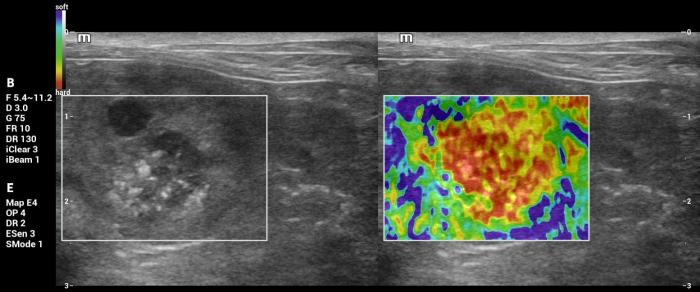

Hallazgos elastográficos (Natural Touch Elastography®): el nódulo presentó una rigidez marcadamente aumentada respecto del parénquima esplénico circundante, con patrón elastográfico heterogéneo (“dureza mixta”), caracterizado por áreas internas de elevada velocidad de onda de corte (Figura 26-27).

Este comportamiento se alinea con los hallazgos reportados para lesiones malignas esplénicas, que tienden a presentar valores superiores a 3 m/s según la evidencia publicada5.

Las mediciones fueron consistentes entre sí y no mostraron artefactos relevantes, lo que respalda la confiabilidad del hallazgo elastográfico.